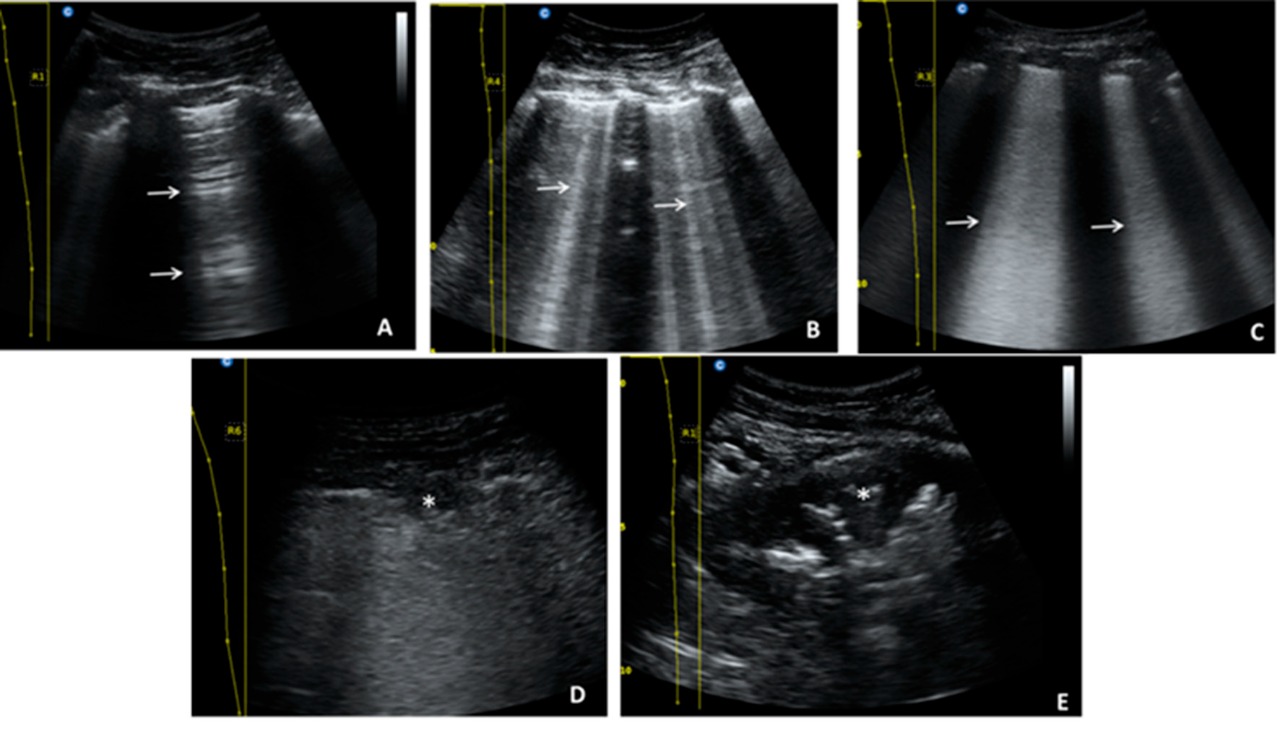

En el análisis univariado se observó una asociación entre la puntuación de la ecografía pulmonar (EP), los niveles elevados de procalcitonina y péptido natriurético cerebral y el ingreso a terapia intensiva. En el análisis multivariado solo la puntuación de EP fue un predictor independiente de requerimiento de terapia intensiva. MEDICINA (Buenos Aires), diciembre de 2021